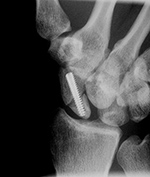

Acutrak screw |

The Acutrak screw stabilizes a scaphoid fracture. |

| Accutrak screws

| The Accutrak screws are used for arthrodesis of the distal interphalangeal joints of the right index and long fingers in a woman with severe osteoarthritis.